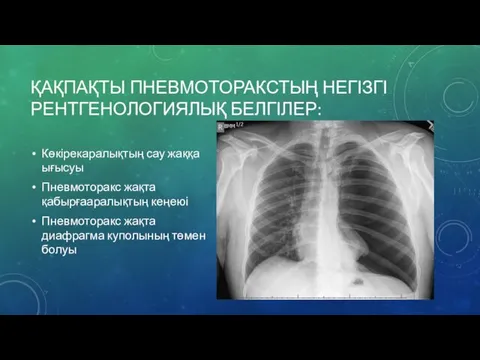

Схемы дыхания: Пневмоторакс на изображениях